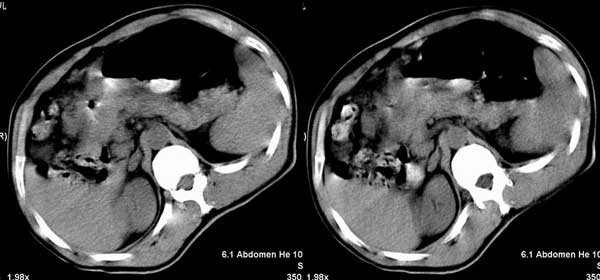

以下是引用听蝉观竹在2005-2-15 23:30:28的发言:[br]胃窦癌。[br]建议做胃镜检查并活检。